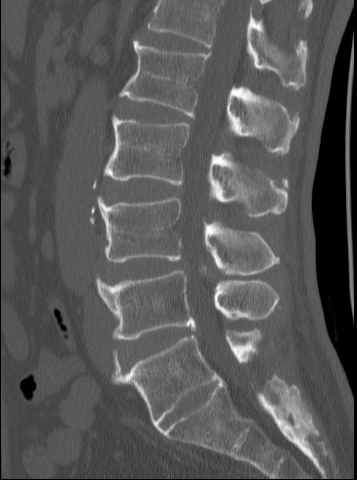

大多数情况下,这些变异是在进行腰部X线、CT或MRI检查时偶然发现的。常见的影像学特征包括:

骶椎腰化表现:

· 第一骶椎(S1)与其他骶椎间保留明显的椎间盘间隙

· S1横突发育不良或与骶骨翼未完全融合

· 第一骶椎与第二骶椎间可见明显的关节间隙

腰椎骶化表现:

· 第五腰椎(L5)横突增大并与骶骨形成骨性连接

· L5与S1椎间盘退化或消失

· L5部分或完全与骶骨融合